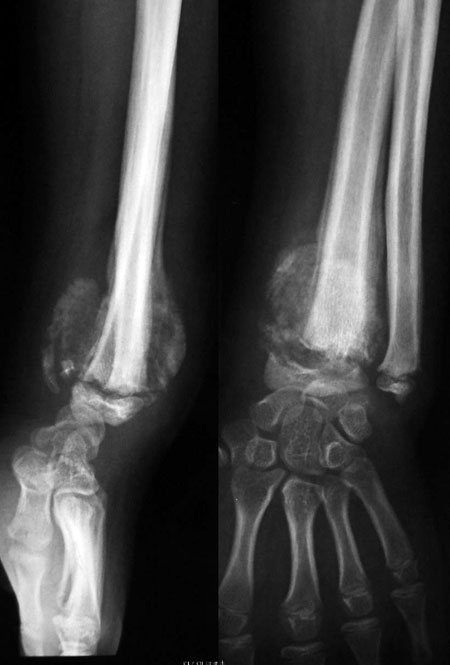

患者 男 14岁 无意中发现左碗肿胀\畸形\无疼痛\无压痛\活动正常3月余.

左桡骨干骺端骨质破坏加成骨,周围有骨膜反应及骨膜三角,并可见软组织肿块及其内的瘤骨.并累及骨骺引起骨骺骨折移位.而且进展较快.男 14岁 无意中发现左碗肿胀\\畸形\\无疼痛\\无压痛\\活动正常3月余.无外伤史.

综合考虑左桡骨干骺端骨肉瘤并骨骺骨折.建议活检.

左桡骨干骺端虫蚀状骨质破坏,边缘欠清,周围软组织肿块有环状钙化,骨干侧有层状骨膜反应,骨骺向外侧移位,考虑:左桡骨干骺端软骨肉瘤并骨骺移位。

干骺端骨质明显破坏溶解缩短,肿块及大量瘤骨形成,骺线赠宽,周围软组织明显肿胀,骨膜反应呈层状。

考虑恶性骨肿瘤,1、骨肉瘤,2、干骺周围型尤文肉瘤。

病理:左桡骨远端新生骨质及少量软骨,横纹肌组织,未见死骨及结核.